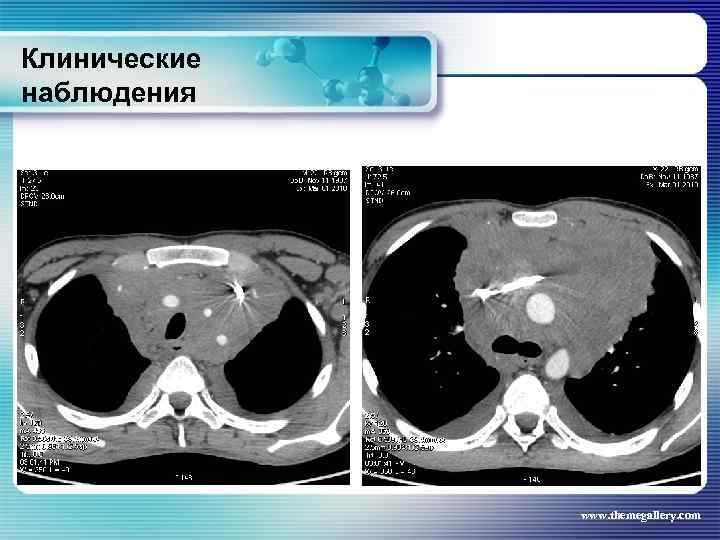

Клинические наблюдения Больной М. , 22 лет По результатам обследования сформулирован клинический диагноз: лимфома Ходжкина, нодулярный склероз, Grade I, III В стадия с поражением подчелюстных, шейных, надключичных лимфатических узлов с обеих сторон, подмышечных, переднегрудных, парастернальных, внутригрудных и абдоминальных лимфатических узлов, средостения. Было проведено 8 циклов BACOPP, на фоне лечения осложнение: полинейропатия рук, а затем асептический некроз головки правой бедренной кости. На фоне терапии отмечена положительная динамика как лабораторных данных, так и результатов лучевого обследования. Констатирована ремиссия www. themegallery. com

Клинические наблюдения Больной М. , 22 лет По результатам обследования сформулирован клинический диагноз: лимфома Ходжкина, нодулярный склероз, Grade I, III В стадия с поражением подчелюстных, шейных, надключичных лимфатических узлов с обеих сторон, подмышечных, переднегрудных, парастернальных, внутригрудных и абдоминальных лимфатических узлов, средостения. Было проведено 8 циклов BACOPP, на фоне лечения осложнение: полинейропатия рук, а затем асептический некроз головки правой бедренной кости. На фоне терапии отмечена положительная динамика как лабораторных данных, так и результатов лучевого обследования. Констатирована ремиссия www. themegallery. com